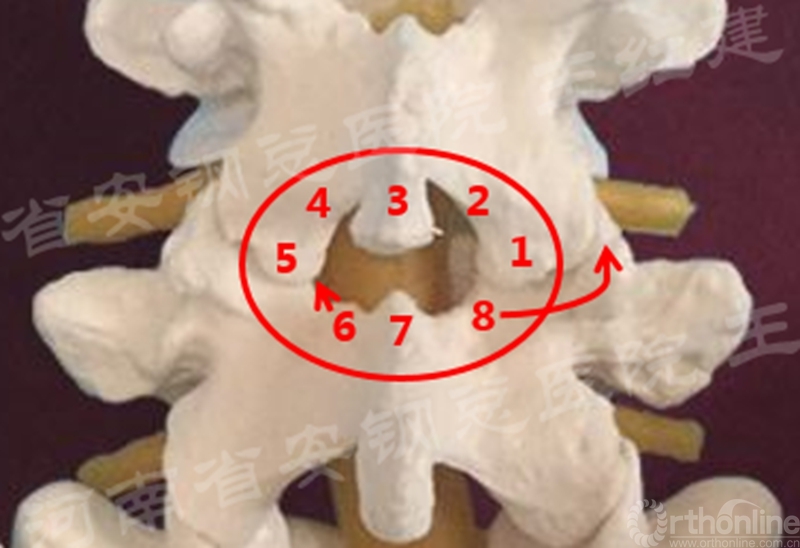

(4) 单侧入路双侧减压

置入内镜通道,用磨钻和枪钳切除上位椎板下缘、下位椎板上缘及突间关节内缘,切除黄韧带,完成单侧入路双侧减压。

单侧入路双侧减压的循序